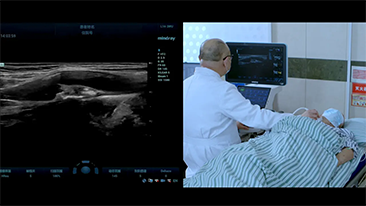

Com que clareza vocĂȘ consegue ver um fĂgado?

Para les?es hepĂĄticas focais, tais como hemangioma ou c?ncer hepĂĄtico, a imagem de contraste por ultrassom desempenha um papel significativo. A tecnologia de imagem por contraste UWN+ n?o linear ultralarga pode ajudar a obter melhor penetra??o e maior rela??o contraste-tecido, com menor MI e maior observa??o do tempo de perfus?o.